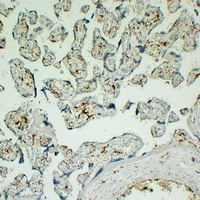

(Dilution: IH: (1/100 - 1/300)Immunohistochemical analysis of CD163 staining in human placenta formalin fixed paraffin embedded tissue section. The section was pre-treated using heat mediated antigen retrieval with sodium citrate buffer (pH 6.0). The section was then incubated with the antibody at room temperature and detected using an HRP conjugated compact polymer system. DAB was used as the chromogen. The section was then counterstained with haematoxylin and mounted with DPX.)